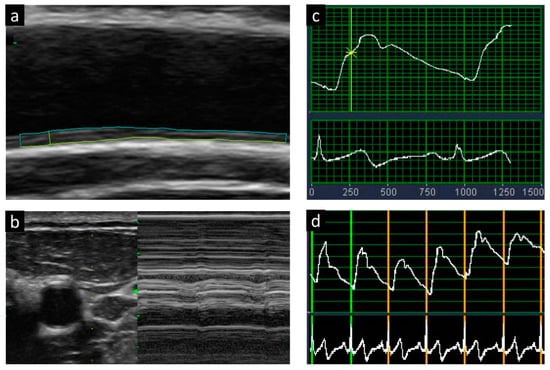

2.3. Ultrasound Examination for Carotid Plaque and Arterial Stiffness